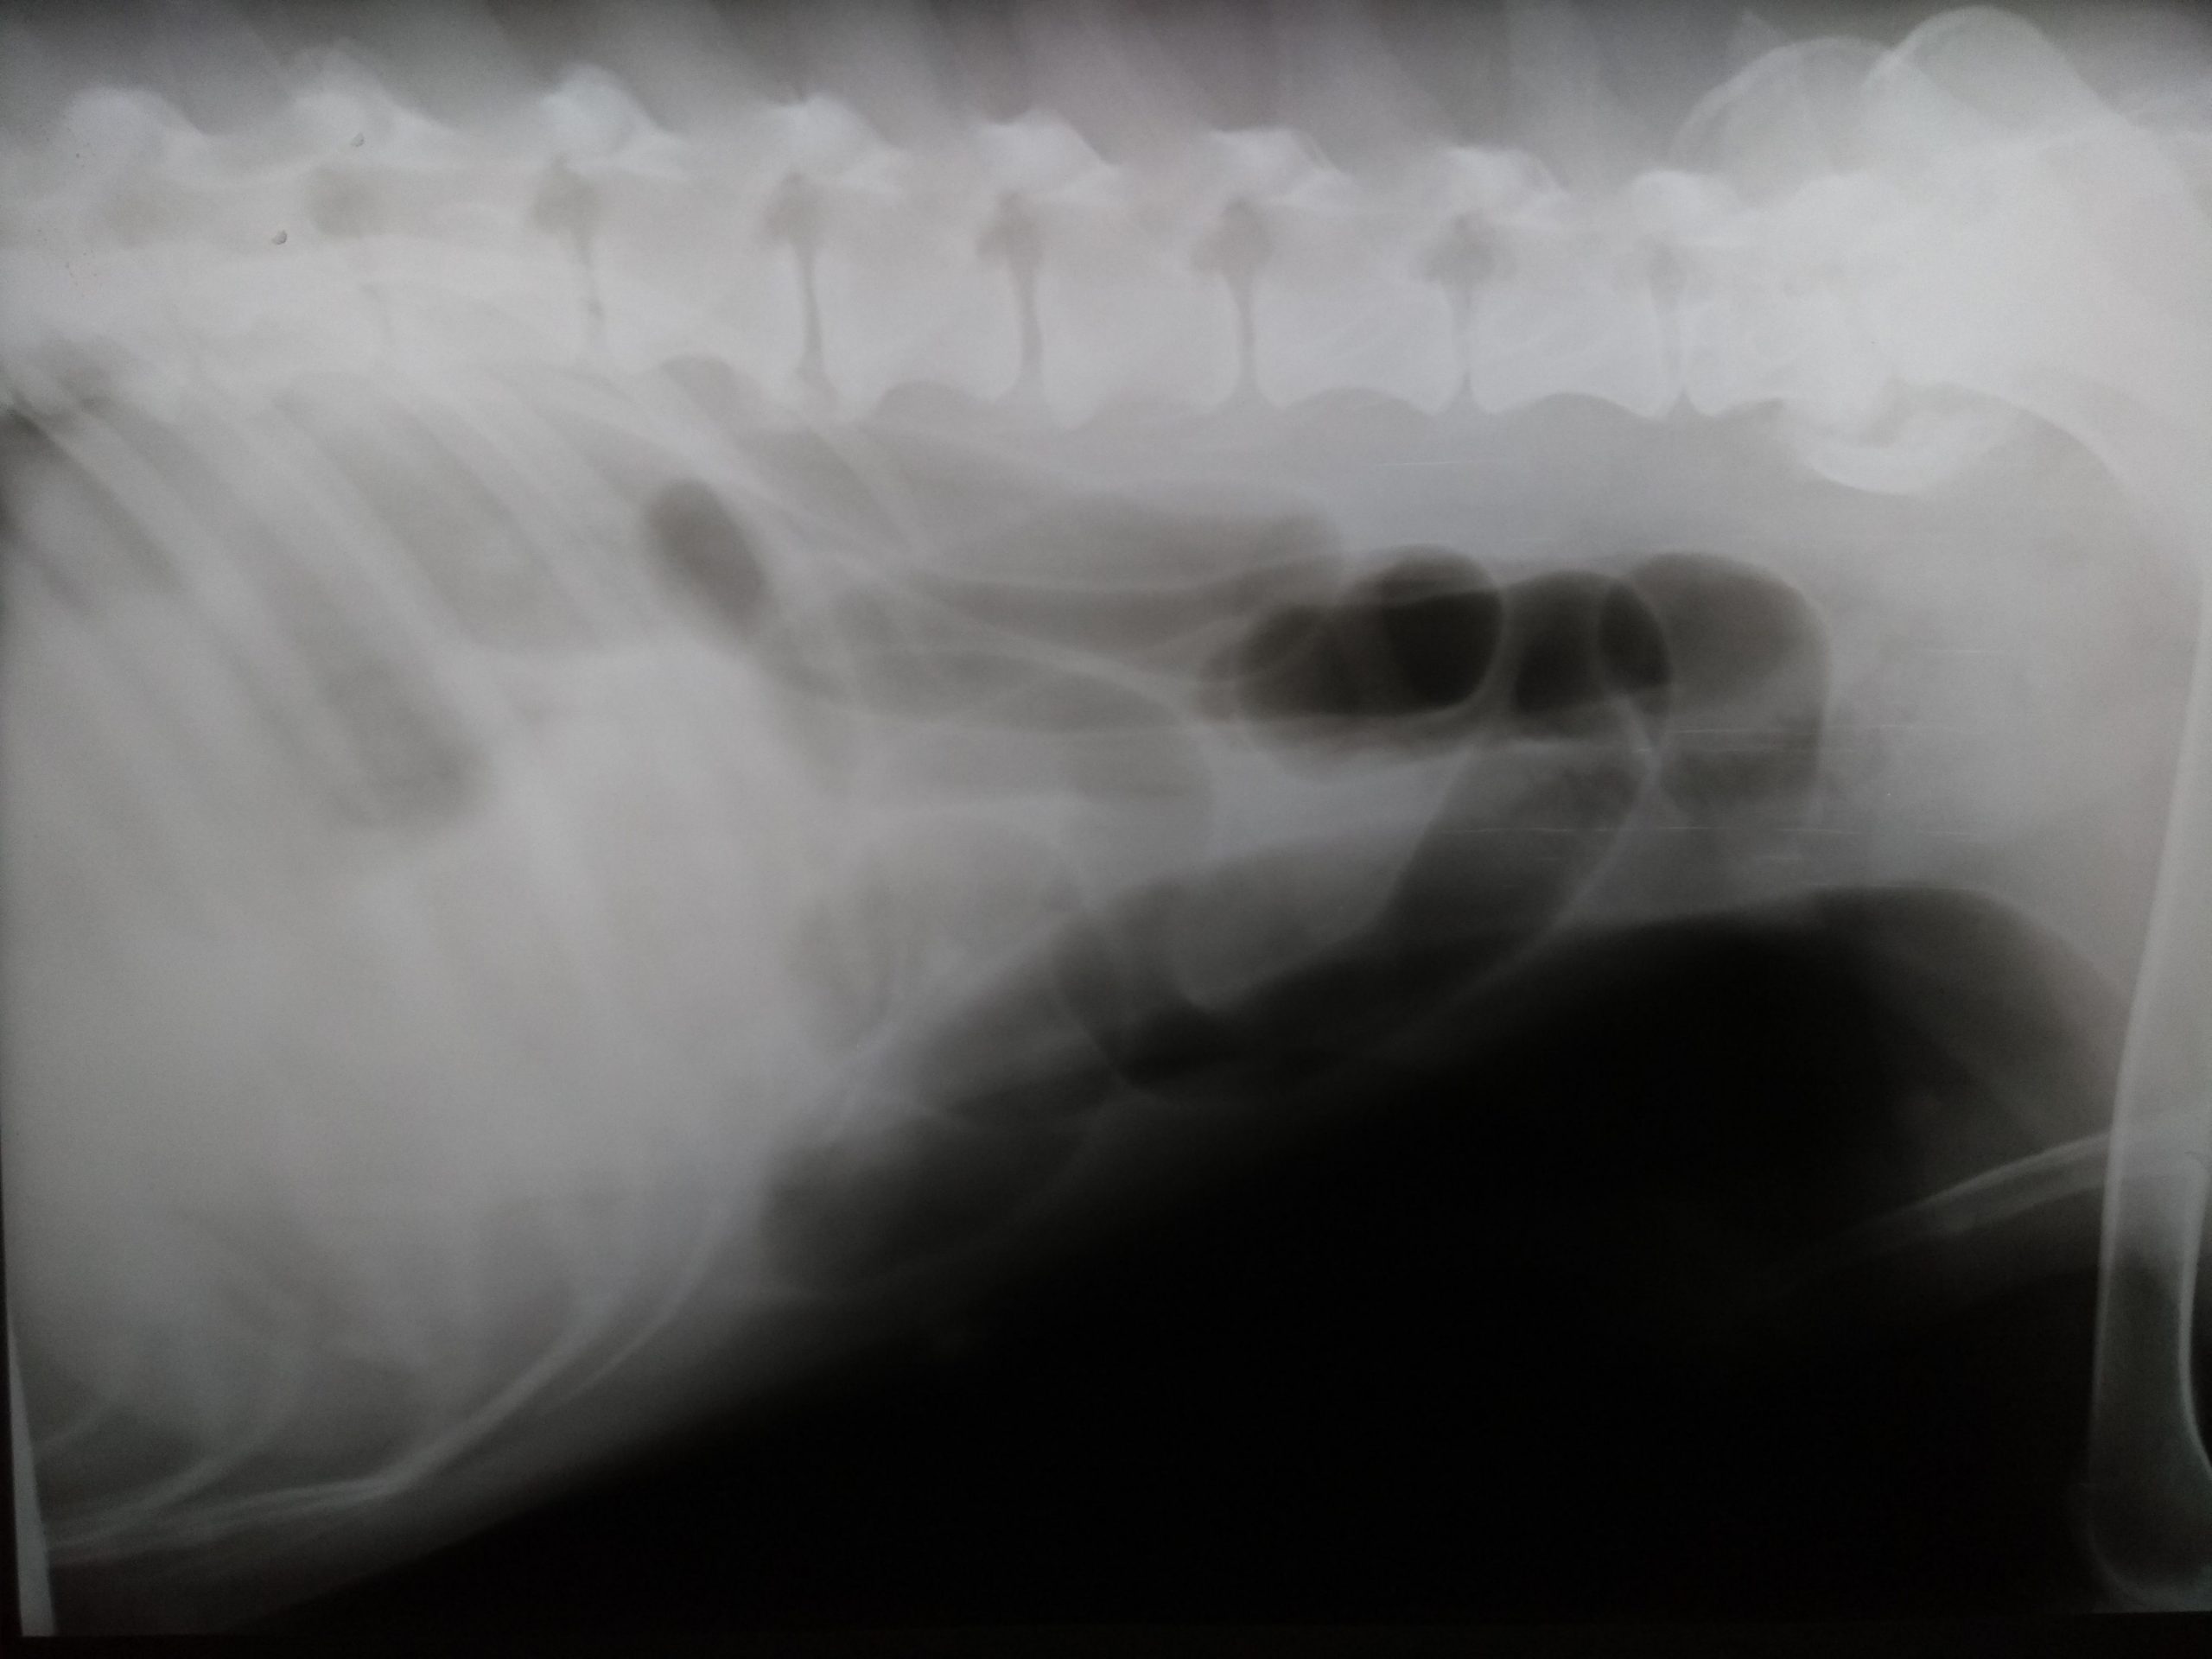

Se realiza estudio radiográfico de tórax y abdominal (no se incluyen todas las radiografías): El estudio no fue concluyente y el veterinario solicita estudio ecográfico abdominal a Dxia.

Radiografía lateral torácica